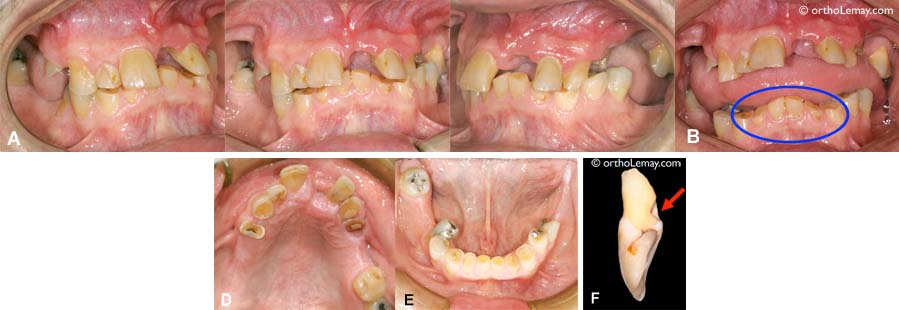

(A) Dentition d’un homme dans la cinquantaine qui est mutilée par l’extraction de plusieurs dents. Il reste peu de dents postérieures. Au cours des années, il y a eu perte de dimension verticale (affaissement postérieur de l”occlusion) de sorte que maintenant, les incisives se surplombent complètement et les prémolaires et molaires inférieures ont “remonté” jusqu’à mordre sur la gencive du haut (flèches). (B) Les corrections orthodontiques ont permis d’inverser cette tendance. (C) La correction de la malocclusion a restauré la dimension verticale. On remarque maintenant que les incisives sont dégagées et que les postérieures inférieures ne mordent plus dans la gencive supérieure. Le dentiste peut maintenant remplacer les dents manquantes à l’aide d’implants dentaires, ce qui était impossible lorsque l’occlusion était affaissée avant le traitement. (D) Des couronnes seront posés sur les implants (flèches).

(A) Cet homme dans la cinquantaine est un bruxeur chronique. L’incisive supérieure gauche était tellement mobile qu’elle est tombée (voir F). Cette dent avait un trou causé par la dent inférieure qui frappait toujours au même endroit. (B) Les incisives inférieures sont usées à 50-70%. (D, E) Aucune dent n’est épargnée par cette usure excessive sauf les dents qui ne touchent pas à une dent opposée.